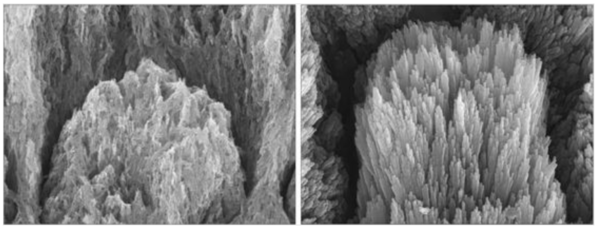

아래 이미지는 법랑질 손상 전후의 변화를 보여준다. 왼쪽은 칼슘과 인산이 빠져나가 표면이 부식된 상태의 치아이고, 오른쪽은 같은 시료에 단백질 젤을 도포해 2주간 굳힌 결과다. 손상됐던 표면이 다시 치밀한 결정 구조를 이루며 재생된 모습을 확인할 수 있다.

부식된 치아(왼쪽)와 단백질 젤 도포 후 2주간 재생된 치아(오른쪽). ⓒ데일리포스트=이미지 제공/Nature Communications